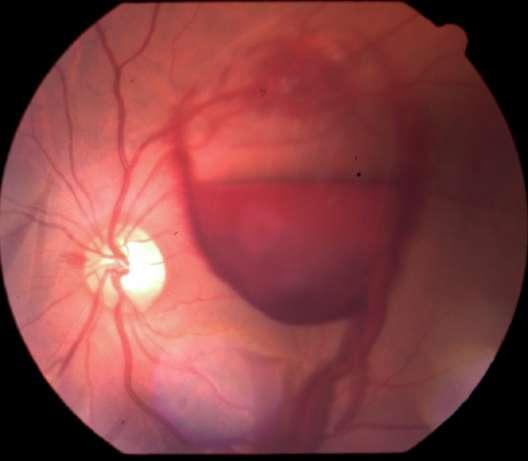

3.A. MELANOMA COROIDEO

Caso aportado por Dra. María José Vergara

Aü Fondo de ojo OD (Imagen A, B y C): Lesión pigmentada localizada a nasal a nivel coroideo, cuyas mediciones son de aprox 10x4mm en sus ejes cefalocaudaltransversal respectivamente

ü Mujer 70 años refiere cuadro de 1 mes de evolución caracterizado por fotopsias y entopsias en ojo derecho con AV conservada.

B C

Imagen D y E

ü Desprendimiento de vitreo posterior

ü Desprendimiento de retina focal inferior exudativa

ü Se constata lesion nasal 3hrs, forma de cupula cuyos diámetros máximos son:

-Al corte longitudinal: Base: 10.85nm, altura 2.58nm

-Al corte transversal: Base 8.81nm; altura 3.64nm con elementos de vascularidad

Dü El melanoma coroideo es el tumor primario intraocular más frecuente en el adulto